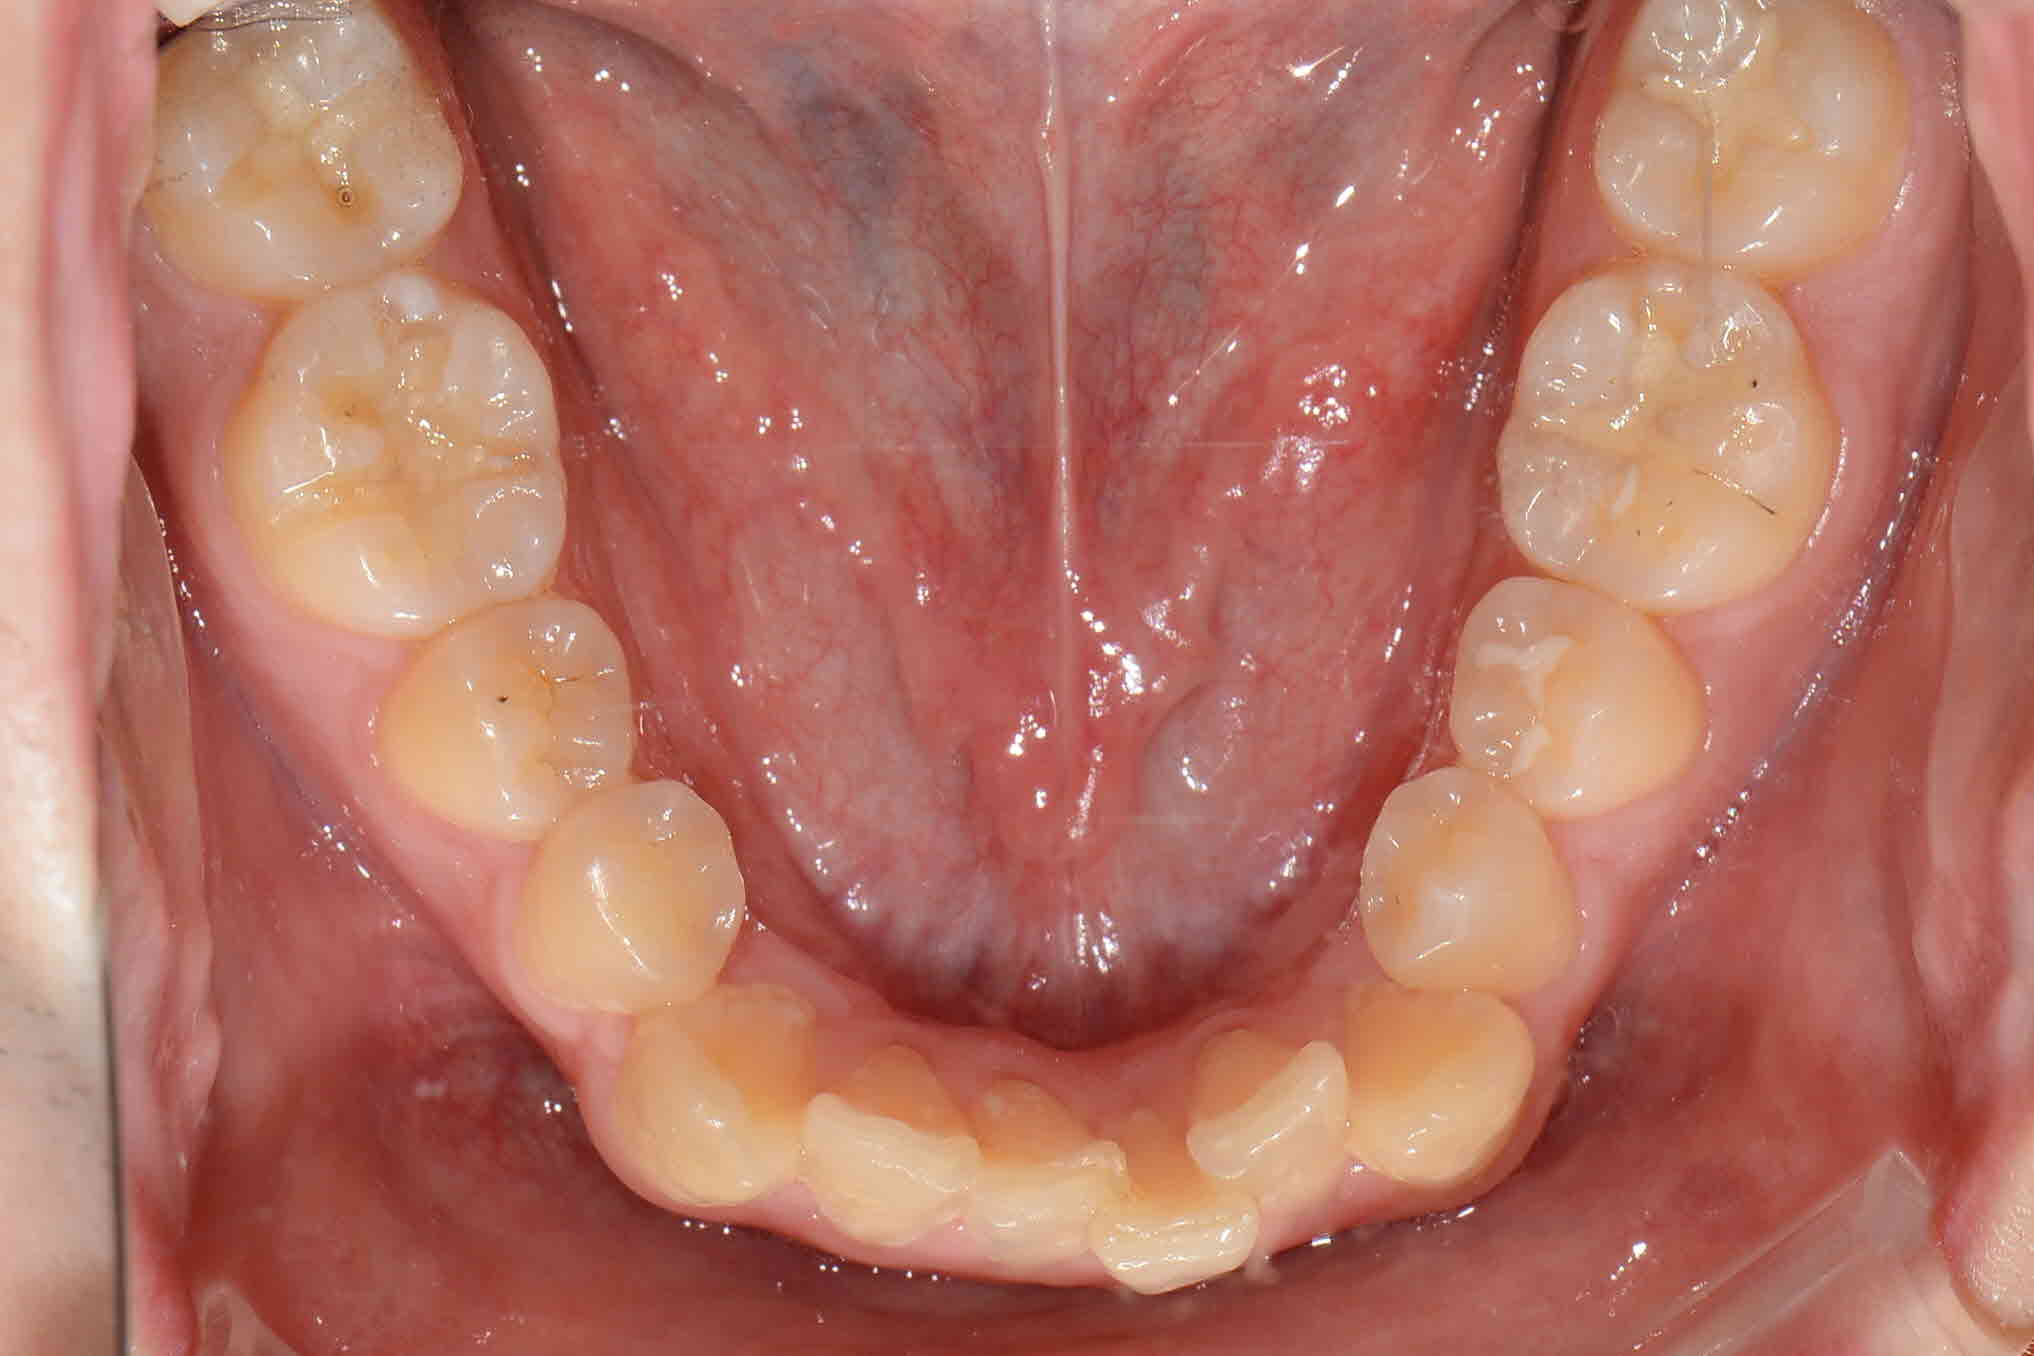

NEW 교정완료)어렸을때는 귀여웠던 덧니, 이제는 골칫거리 덧니...♨

남자다운 모습, 귀엽고 앙증맞은 모습을 다 가지고 계신 임**님! 어렸을적에는 잘 몰랐지만 사회로 나오면서 컴플렉스의 주된 원인이 었던 덧니때문에 내원해주셨는데요! 임**님께서 더 이상 스트레스 받지 않으시도록 교정치료를 통해 덧니를 완전히 해결해드리겠습니다.

교정시작 교합면

2016년 9월 교합면

2017년 02월 교합면

2017년 06월 교합면

교정완료 교합면